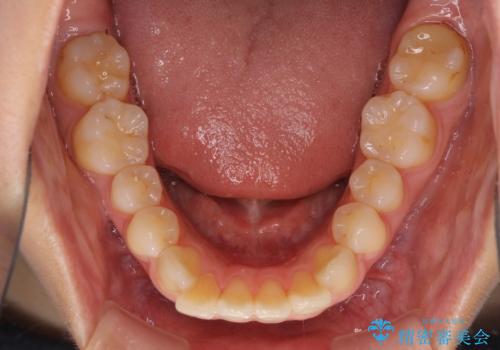

- 前方に傾斜した上下の前歯を気にして来院された患者様です。

唇の閉じにくさや横顔のシルエットが気になるような突出感ではなかったため、インビザラインを用いて、歯列の遠心移動とIPR(歯と歯の間を削る)により前歯の傾斜を改善していくこととしました。